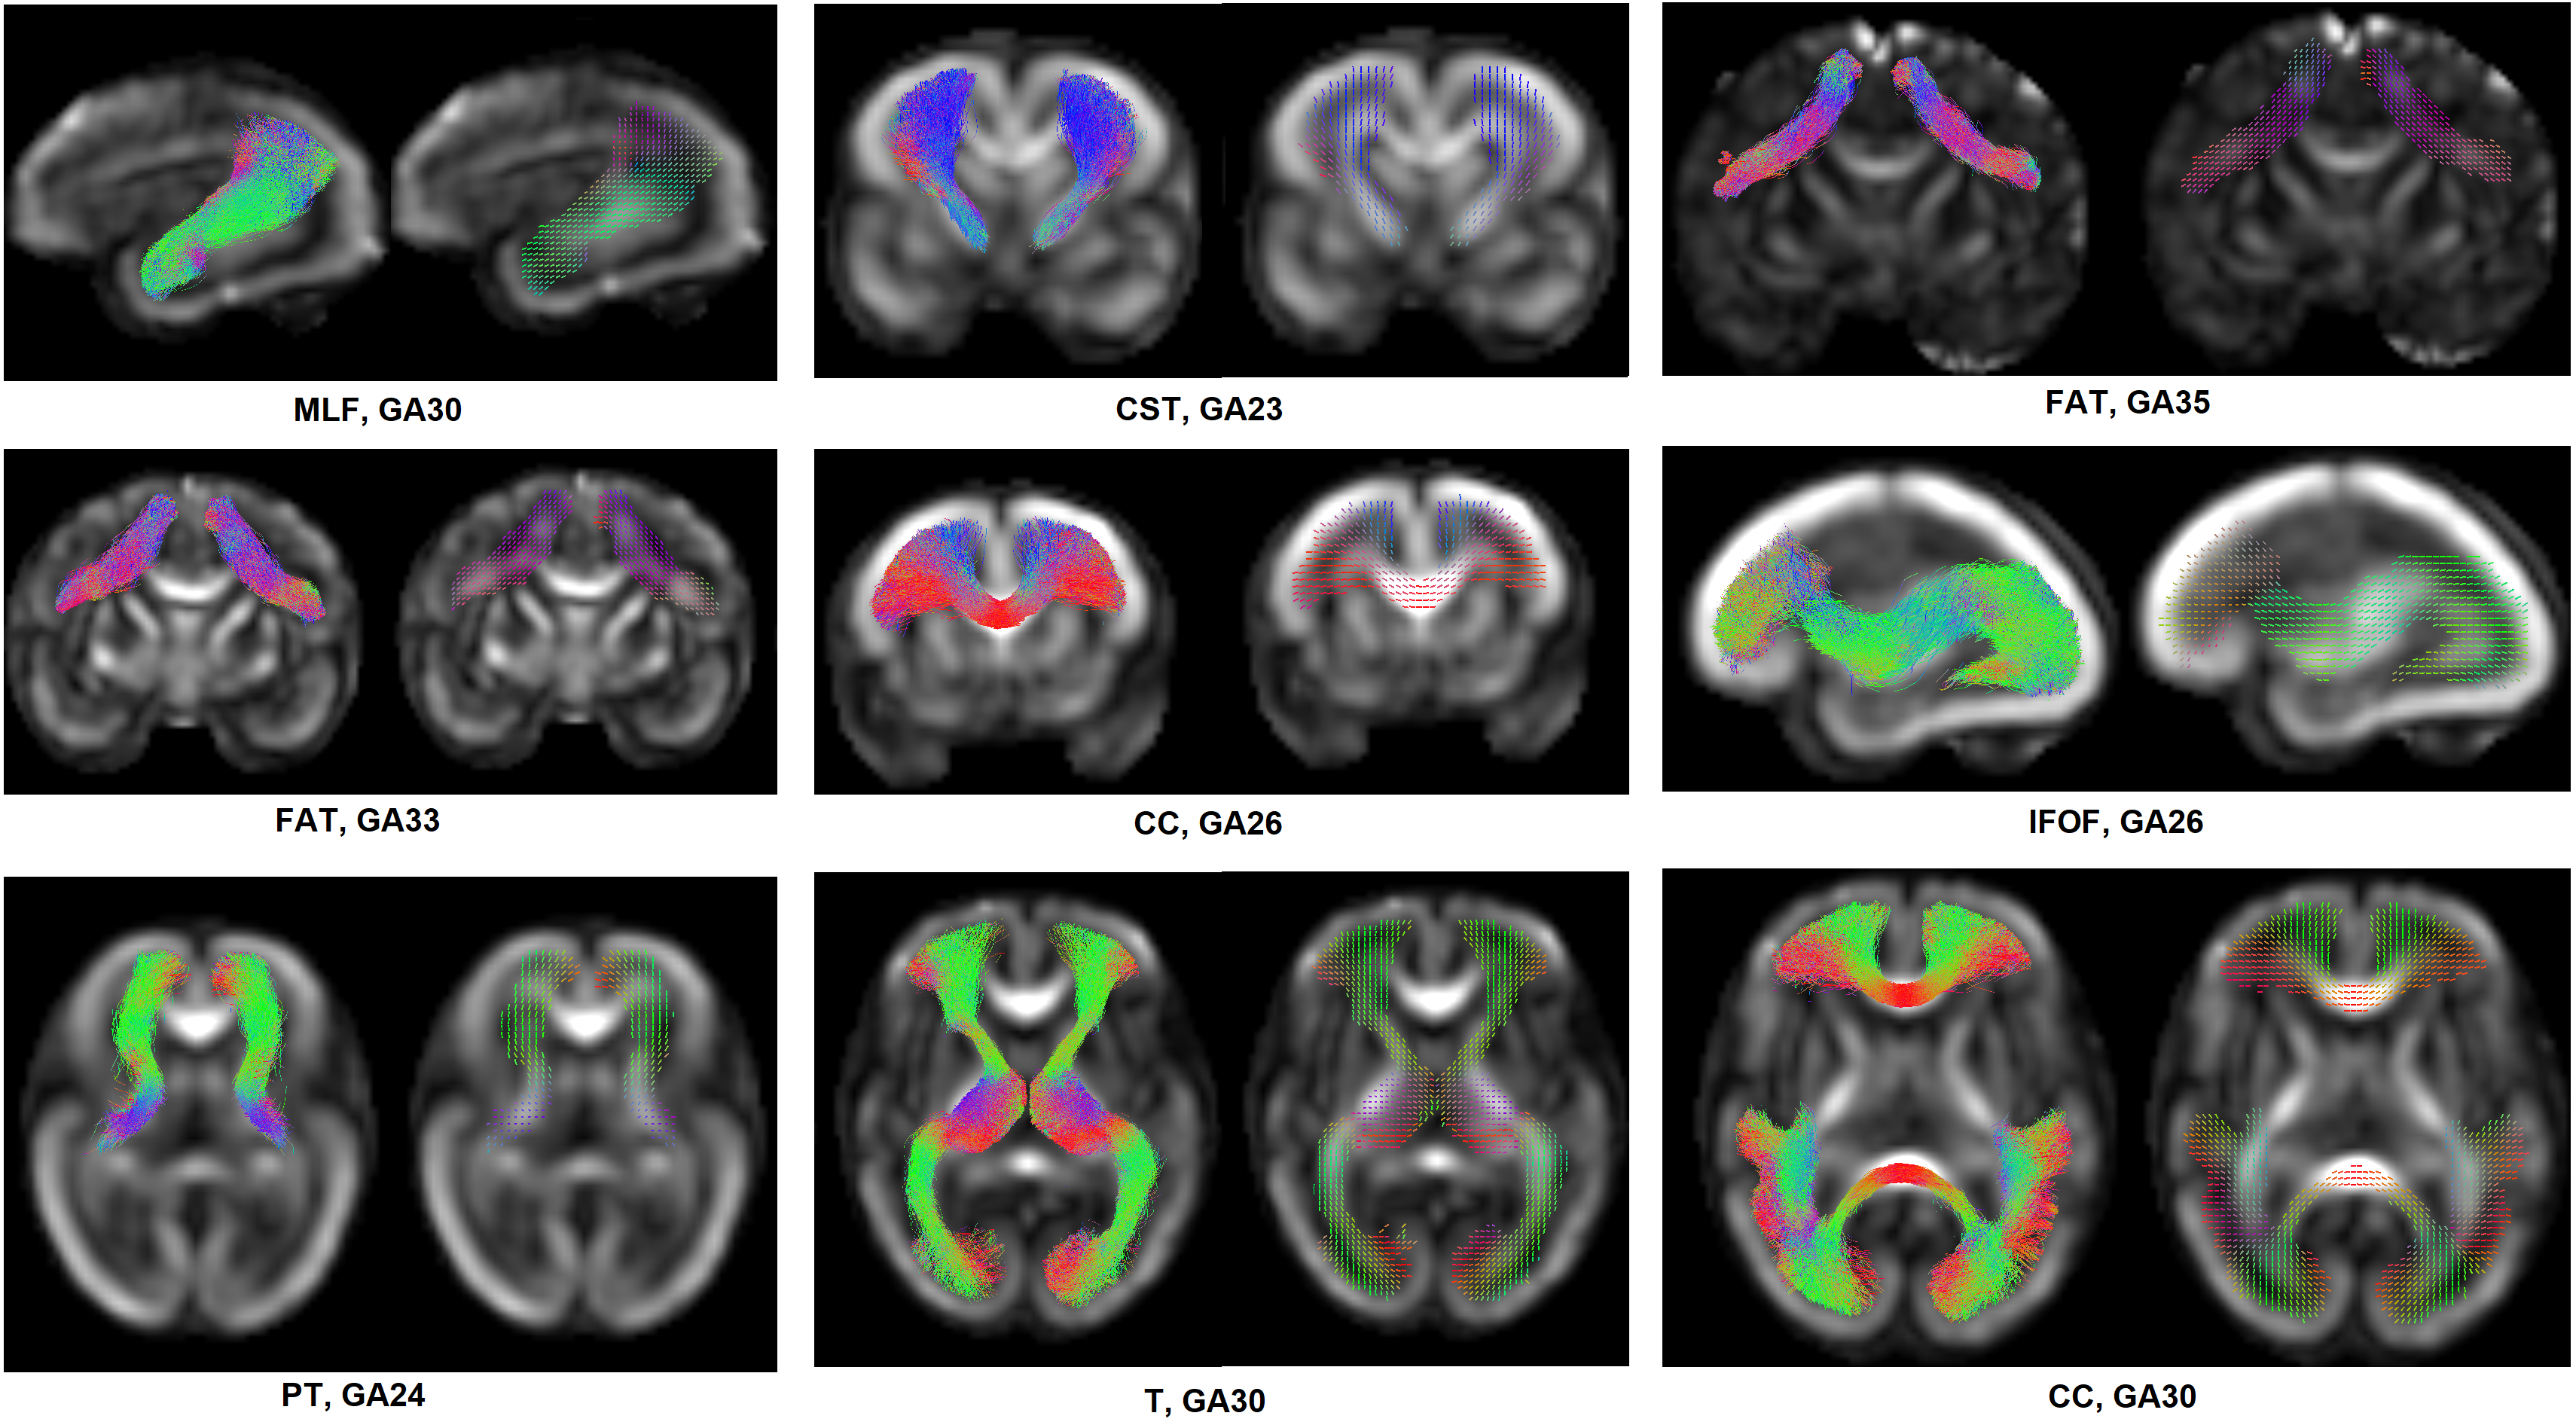

For each tract, we applied the following three processing steps to compute a TOM. (1) Compute the tract density map, showing the number of streamlines crossing each voxel. Compute the histogram of the non-zero density values and eliminate voxels where the streamline density is below the 5th percentile of density values. This operation eliminates voxels that contain spurious streamlines that are mainly tractography false positives. (2) Reorient all streamlines in the tract so that they all run in the same direction. Then, in each voxel i𝑖i, compute the unit vector uijsuperscriptsubscript𝑢𝑖𝑗u_{i}^{j} representing the direction of streamline j𝑗j from the considered tract in that voxel. Compute the mean of uijsuperscriptsubscript𝑢𝑖𝑗u_{i}^{j} to obtain that voxel’s mean direction u¯isubscript¯𝑢𝑖\bar{u}_{i}. The arithmetic mean represents the maximum likelihood estimate of the tract orientation, assuming that streamline directions follow a von Mises–Fisher distribution. (3) Apply non-local denoising [70] on u¯¯𝑢\bar{u} to obtain a smooth TOM. Figure 1 shows streamline bundles for several tracts extracted from whole-brain tractograms and their corresponding TOMs computed using the proposed method.

Refer to caption

Figure 1: Tract orientation maps (TOMs) computed for example tracts. Each subfigure shows the bundle of streamlines extracted for that tract and the TOM computed from the streamlines. The name of the tract and gestational age (GA) for the fetus are shown under each subfigure.